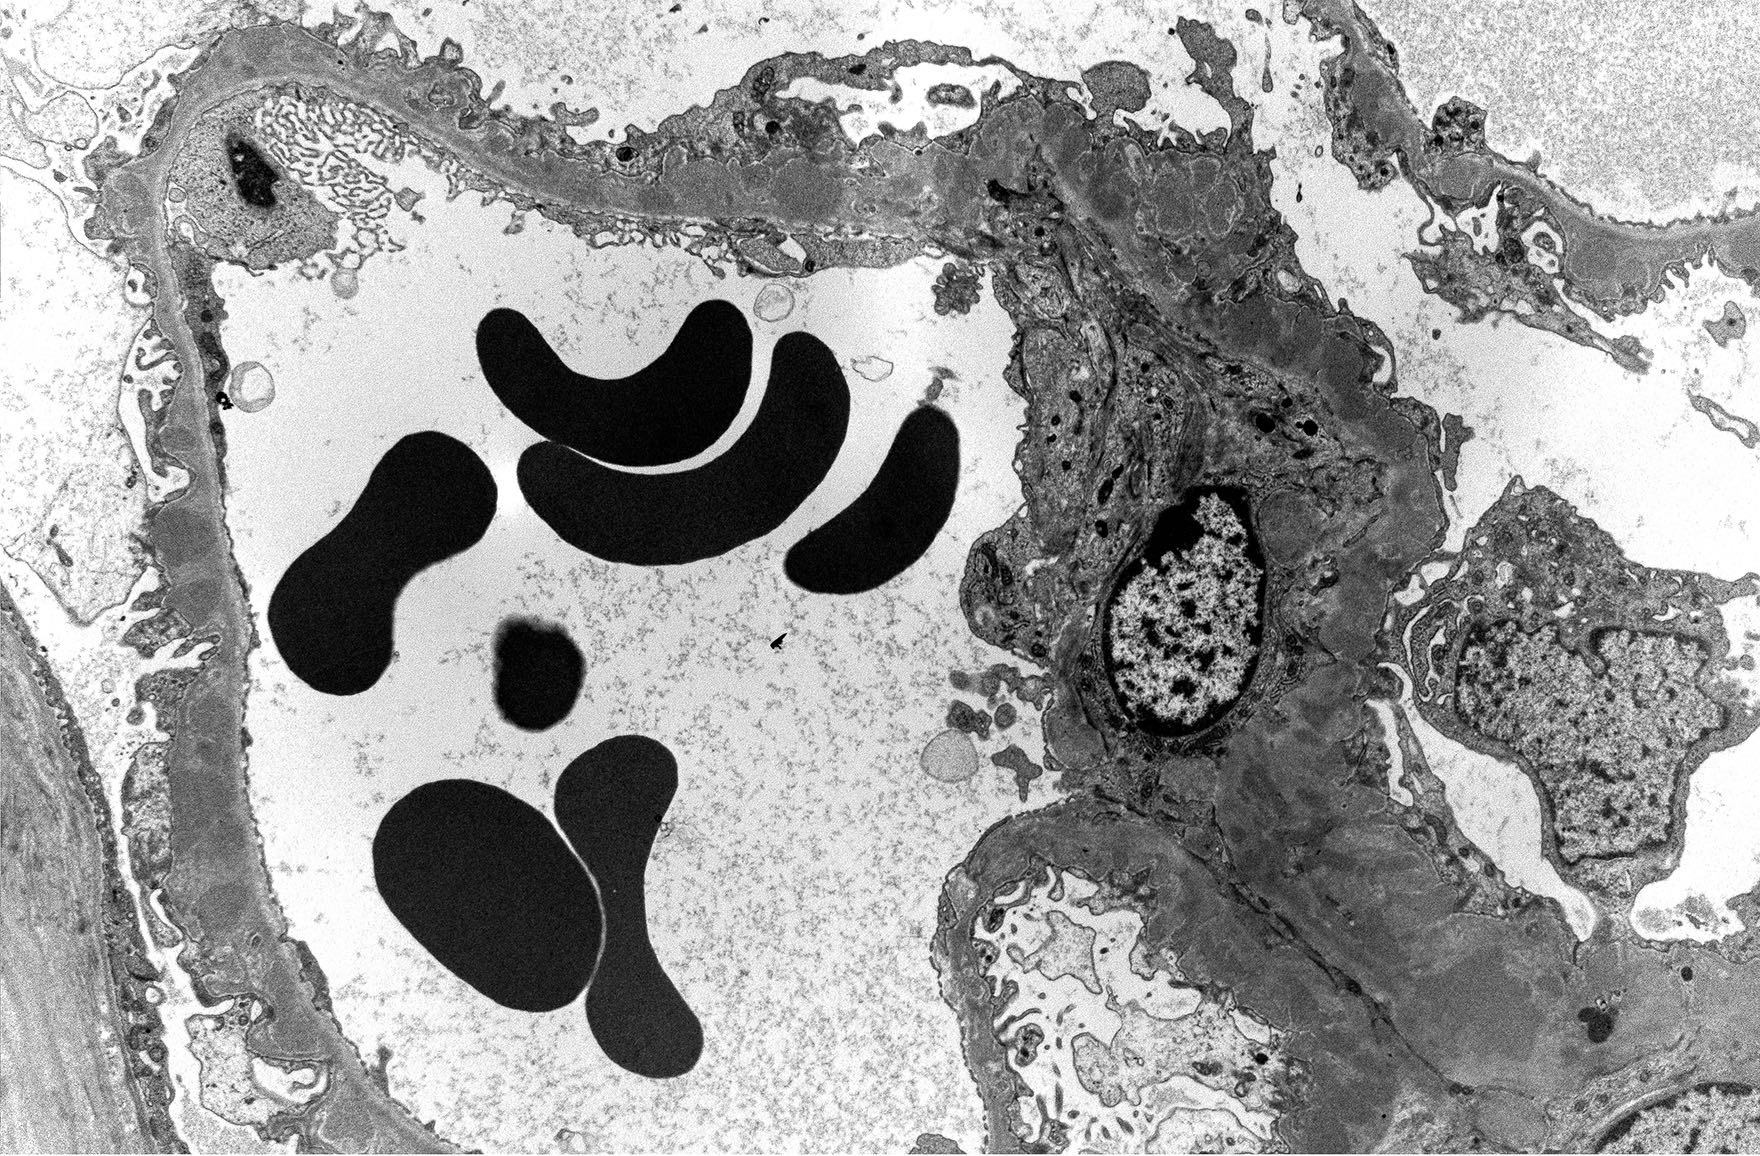

Electron microscopy description

- Finalizes the classification of lupus nephritis for a given case

- Granular electron dense deposits (smaller in LN classes I - II and larger in classes III - IV) are seen in subepithelial, intramembranous, subendothelial and mesangial locations; locations are important in determining the LN class

- Subepithelial immune deposits show adjacent neomembrane formation

- Immune deposit substructure may be present

- Tubuloreticular inclusions: reticular aggregates of branching membranous tubule within the cisternae of endoplasmic reticulum found within the endothelial cells are useful in establishing the diagnosis of lupus erythematosus; are also found in other conditions with elevated levels of interferon (Pathology 2019;51:727)

Electron microscopy images

- Electron microscopy: Glomerular basement membranes are of normal thickness. Numerous subendothelial electron dense (immune complex) deposits are seen. There is mild segmental podocyte foot process effacement. Capillary lumens are patent. The mesangium shows a moderately expanded mesangial matrix and contains large electron dense deposits.

Biopsy is done on a patient with a history of systemic lupus erythematosus and nephrotic syndrome. Electron microscopy reveals the findings shown above. Which complication is the patient predisposed to?

Practice answer #3

D. Renal vein thrombosis. The risk of deep vein thrombosis, especially renal vein thrombosis, is increased in patients with lupus nephritis classes III, IV and V but especially in patients with membranous lupus nephritis (class V). Answer A is incorrect because fibromuscular dysplasia of the renal artery is a noninflammatory process leading to arterial stenosis. Answer B is incorrect because oxalate nephropathy is associated with deposition of calcium oxalate crystals in kidney tubules. The etiology includes primary hyperoxaluria, enteric hyperoxaluria (fat malabsorption) and ingestions (e.g., ethylene glycol poisoning). Answer C is incorrect because papillary necrosis is a complication of NSAID nephropathy.